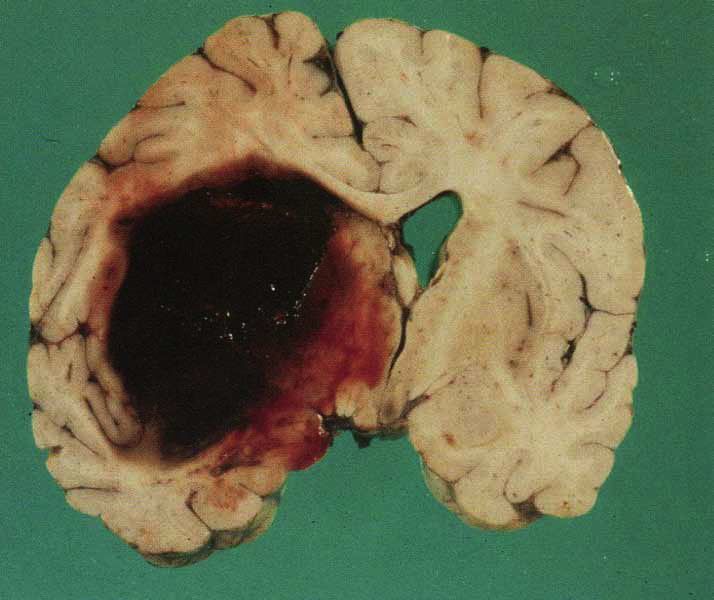

Cerebral Amyloid Angiopathy

- note large lobar hemorrhage